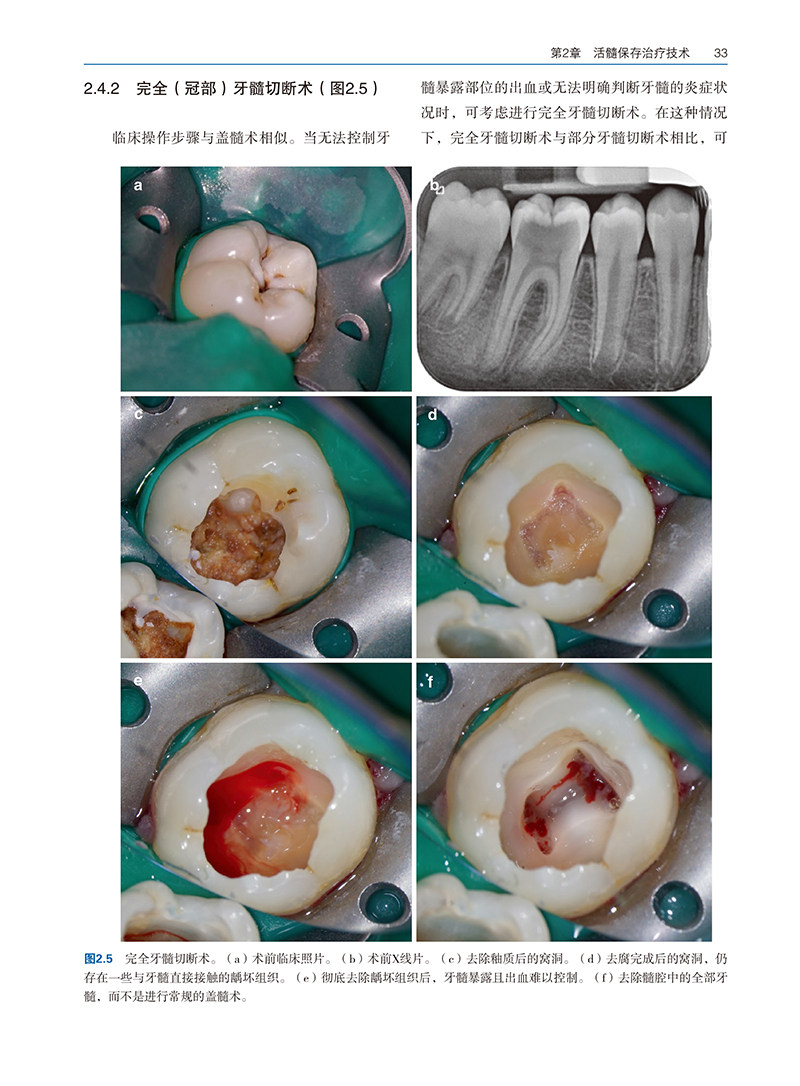

第2章 活髓保存治疗技术